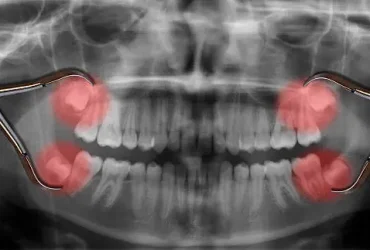

ฟันคุดคือ ฟันกรามซี่ในสุด ทั้งหมด 4 ซี่ บน ล่าง ซ้าย ขวา ไม่สามารถขึ้นได้ตามปกติเพราะพื้นที่ไม่เพียงพอให้ฟันสามารถขึ้นมาได้ บางซี่อาจจะโผล่ขึ้นมาเล็กน้อย และบางซี่ถูกฝั่งอยู่ในกระดูดขากรรไกร อาจจะขึ้นตรง เอียงหรือนอนในแนวราบส่วนใหญ่ฟันคุดมักพบว่าอยู่ที่ฟันกรามซี่ล่างในสุดและพบมากสุดในช่วงอายุ ประมาณ 16 – 25 ปี หรืออาจจะช้ากว่านั้น